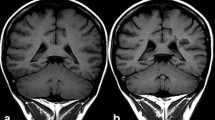

The use of gadolinium-based contrast agents (GBCA) in humans [1, 2], dramatically expanded the diagnostic capabilities of magnetic resonance imaging (MRI) and 30 million doses of GBCA are administered annually in both clinical and research settings [3]. Initially, it was thought that the only risks associated with these agents would be allergic reactions and similar acute adverse events. The first case of nephrogenic systemic fibrosis (NSF) [4] was reported in 1997 and 9 years later this condition was eventually linked to gadolinium (Gd) exposure [5,6,7]. The incidence of NSF has been lowered dramatically by decreasing the dosage and limiting administration of these agents in high-risk patients. Over the past 3 years, evidence for deposition of these agents in the brain during clinical use has come to light: first on imaging as high-T1 signal intensity in the dentate nuclei (DN) (Fig. 1) and globus pallidus (GP) and subsequently the detection of Gd in both autopsy and biopsy tissue studies [8,9,10]. The question as to whether there is a clinical syndrome associated with Gd deposition remains open, although no definitive evidence has so far been published [11,12,13,14,15].

Unenhanced axial T1 spin echo image (1.5 T, 5 mm, TR: 608 TE:15) demonstrating high signal in both dentate nuclei (white arrows). This patient was being followed up for a pineoblastoma and had also undergone one radiotherapy session. He was imaged four times using a linear agent and once using a macrocyclic agent